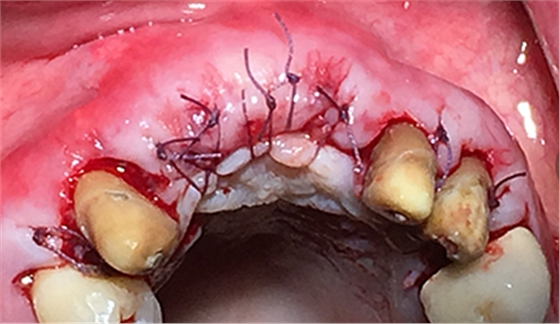

這時候縫合可能還會存在一些軟組織張力,這時候最好的辦法不是唇側(cè)減張縫合,看我的方法,既可以達到減張的目的又可以保證牙槽嵴頂角化齦充足。